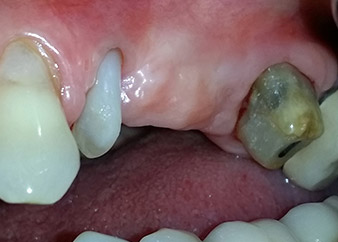

Междинен резултат след два месеца

Фигури 17 и 18 показват клиничния резултат два месеца след операцията. Зъб 24 показва намалена подвижност на Милър клас 1 и меките тъкани не са възпалени. Сондирането е избегнато на този етап, за да се избегне повторно възпаление и нарушение на епителната надстройка. Планиран е контролен преглед за повторно отваряне и поставяне на оздравителни абатмънти, шест месеца след поставяне на имплантите.

Два месеца след операцията, пациентката не чувства болка.

Фиг. 17: Два месеца след операцията, пациентката не чувства болка и зоната не е възпалена.

след операцията

Фиг. 18: Зъб 24 вече показва по-малко подвижност.

Прогноза и опции за възстановяване

На прегледа след два месеца, мобилността на останалия "дентален елемент" 24 вече е намалена от Милър 2 на Милър 1. Захващането на меките тъкани е на нивото на съседния зъб 23. Освен това, няма ендодонтски или периодонтални симптоми, така, че прогнозата трябва да се коригира.

Въпреки това, тъй като голяма част от букалната и проксималната кост липсва и композитното изграждане се простира до апикалната част корена, не се очаква по-високо ниво на захващане в следствие на биологични причини (Sculean et al., 2008).